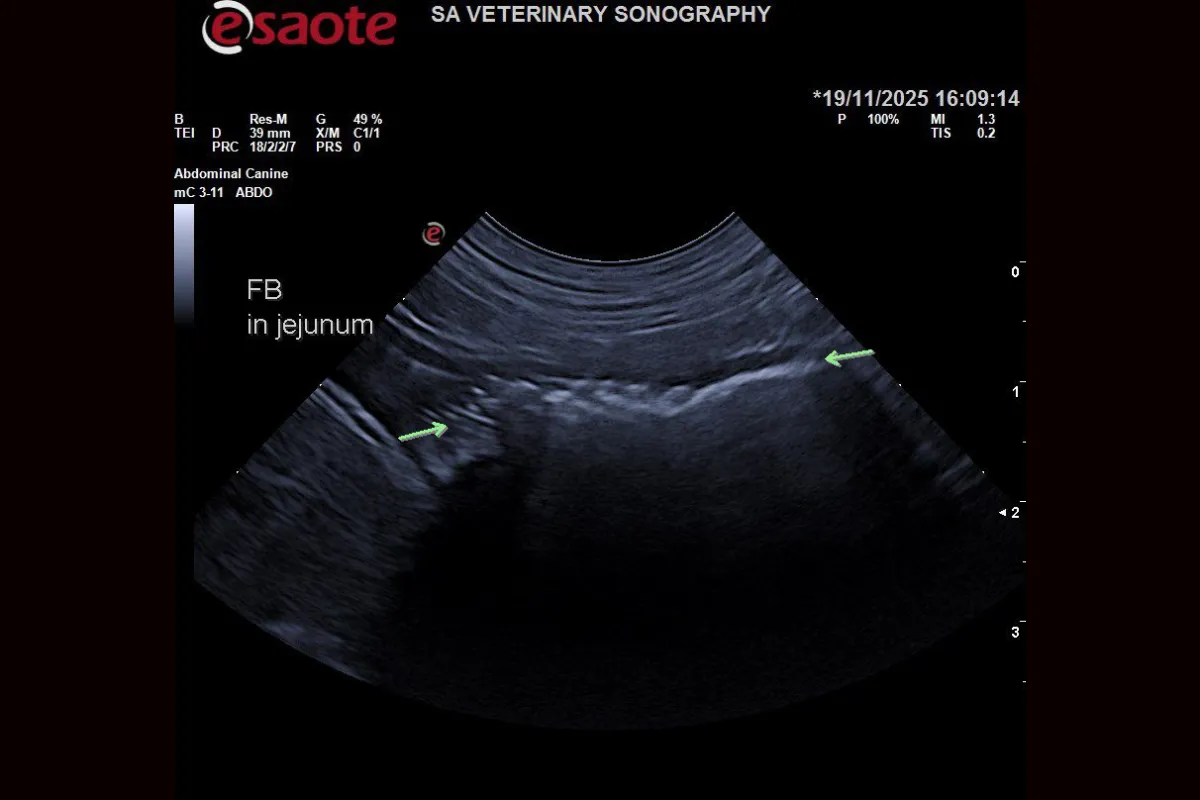

A focused abdominal ultrasound was performed, and the findings were decisive:

• A strongly shadowing object was lodged in the small intestine (jejunum).

• A clear obstructive pattern was present, with a dilated intestine proximal to the object and a normal intestine distal to it.

• No free abdominal fluid or complicating features were noted.

The scan confirmed the obstruction and identified its precise location, providing the vet with immediate and actionable information.